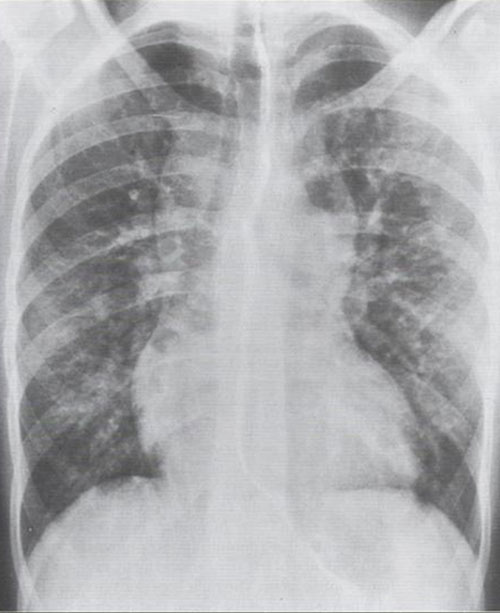

Total anomalous pulmonary venous connection (tapvc) or return (tapvr) is a rare congenital cyanotic heart defect where the four pulmonary veins do not drain into the left atrium but via unique pathways into the right atrium or systemic veins. In a child born with total anomalous — which means abnormal — pulmonary venous return (tapvr), the pulmonary veins connect to other veins and ultimately drain their blood into the right atrium. Sung wk, au v, rose a. Anomalous pulmonary venous return refers to conditions where some or all of the pulmonary veins have their blood return to the right atrium, either directly or through the svc or an abnormal, connecting venous structure. Cases of partial anomalous pulmonary venous return. Total anomalous pulmonary venous connection(tapvc). Total and partial anomalous pulmonary venous conne. Pulmonary hypertension in a patient with partially anomalous pulmonary venous return.

All have shunt through lungs to r side of heart. Anomalous pulmonary venous connection (or anomalous pulmonary venous drainage or anomalous pulmonary venous return) is a congenital defect of the pulmonary veins. Total anomalous pulmonary venous connection (tapvc) is a condition in which all the pulmonary venous return drains either directly into the right tapvc is also referred to as total anomalous pulmonary venous return. All must also have r to l shunt for survival. Total anomalous pulmonary venous return (tapvr) is a condition in which the blood vessels from the lungs take an in tapvr, there is a problem in the usual connection between the blood vessels (pulmonary veins) coming from the lungs to the left atrium. All these partially anomalous pulmonary venous returns are left to right shunts, but when small, they are clinically insignificant. Total anomalous pulmonary venous return:

All these partially anomalous pulmonary venous returns are left to right shunts, but when small, they are clinically insignificant anomalous pulmonary venous return. Patients with obstructed total anomalous pulmonary venous return are usually critically ill with severe cyanosis and often have very unstable blood pressure.